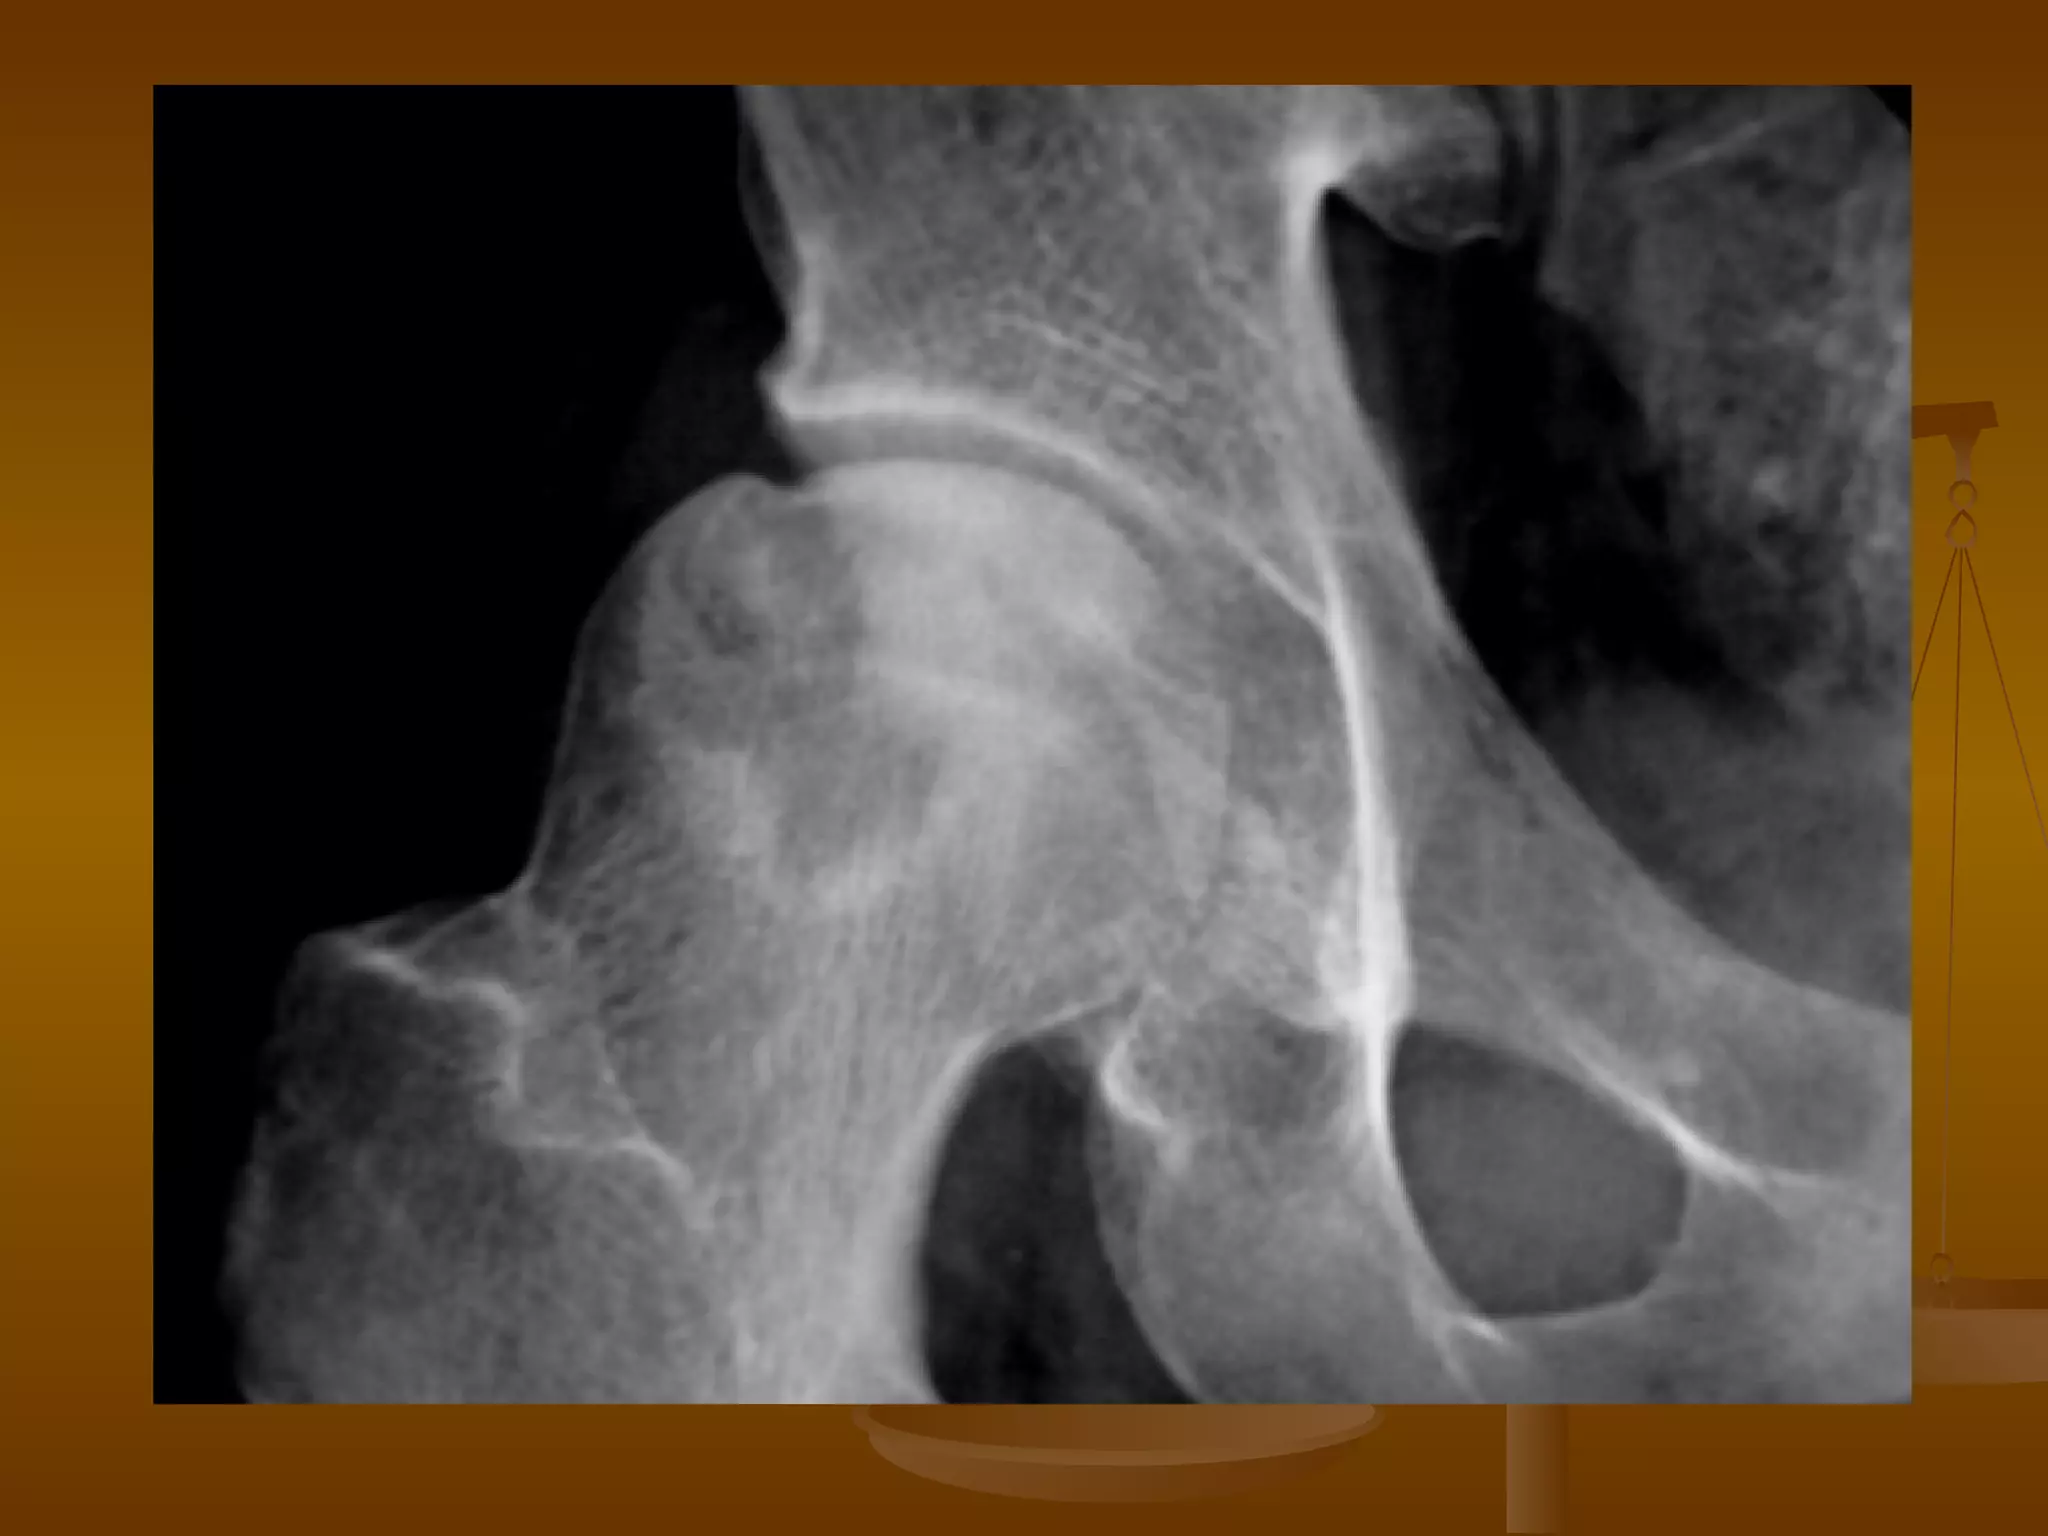

X 线诊断 X 光表现—早期 股骨头表面光整,无变形,髋关节间隙不狭窄,股骨头骨质无改变。 仅见股骨头弥漫性骨质稀疏,小梁模糊。 局限性骨密度增高、硬化,在骨密度增高区的边缘有斑片状密度减低区。 股骨头关节面皮质下出现星月形透亮区。病变常见于股骨头外上部负重区,病变范围多小于股骨头关节面 1/2 。

X 线诊断 X 光表现—中期 髋关节间隙不狭窄,股骨头轻度变形,出现轻度台阶征,股骨头尚未明显塌陷、碎裂。 股骨头密度不均匀,出现囊样或扇形骨质破坏区,周围可有高密度新骨增生。 病变常位于股骨头上部,累及范围多小于股骨头关节面 2/3 。

X 线诊断 X 光表现—晚期 股骨头明显变形、压缩、塌陷、骨密度不均匀。 病灶可累及整个股骨头,最终出现股头分节、碎裂。 并导致髋关节间隙狭窄和退行性骨关节炎。